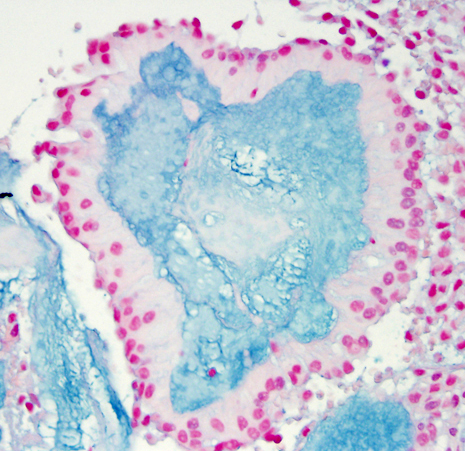

Choroid plexus tumors affect mostly children and young adults. They are a continuum which includes choroid plexus papilloma-CPP (WHO grade I), atypical CPP (WHO grade II) and choroid plexus carcinoma-CPC (WHO grade III). CPC is most common in very young children and is seen in older patients. In children, CPP and CPC arise in both, lateral and fourth ventricles. In adults, CPP is more frequent in the fourth ventricle and sometimes arises in the cerebellopontine angle. CPP is seen in the Aicardi syndrome, an X-linked syndrome in females, characterized by agenesis of the corpus callosum, chorioretinal lacunae, and infantile spasms. CPC occurs in the rhabdoid tumor predisposition syndrome, caused by germline mutations of the INI1 gene. Choroid plexus tumors cause hydrocephalus and increased intracranial pressure by blocking CSF pathways and by oversecreting CSF. CPC can also seed the subarachnoid space. Both, CPP and CPC have a papillary basic structure. In CPP the papillae are covered by a single layer of benign epithelial cells, similar to normal choroid plexus. In CPC the tumor cells are multilayered, atypical, and mitotic, and the papillary structure may be effaced such that the tumor appears solid.